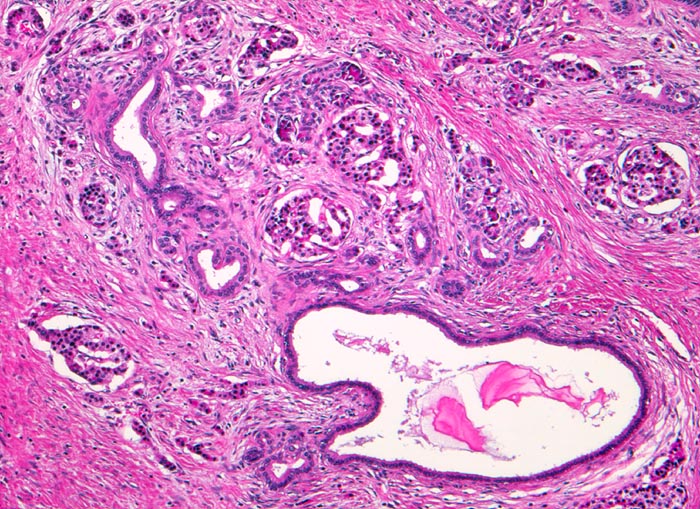

Die Nekrosen des interlobulären Gewebes und der interlobulären Gänge bei ethylischen Pankreatitisschüben führen primär zu einer interlobulären Fibrose und interlobulären Gangstrikturen. In den betroffenen interlobulären Gängen führt der Sekretstau zur Konkrementbildung (verkalkte Proteinpräzipitate). Wie bei einer chronisch obstruktiven Pankreatitis kommt es in den unvollständig drainierten Läppchen zu einer Atrophie der Azini verbunden mit intralobulärer Fibrose. Letztere Areale enthalten schliesslich nur noch Reste unregelmässig verteilter Gänge, Inseln, Nerven und Gefässe. In vielen Fällen lassen sich extrapankreatische Pseudozysten gefüllt mit nekrotisch-hämorrhagischem Detritus in der Nachbarschaft der fibrosierten Bezirke nachweisen.

Breite Bänder von sklerosiertem zellarmem Bindegewebe verlaufen zwischen den Läppchen.

Atrophie des exokrinen Pankreas.

Erhaltene Inseln und Gangstrukturen.

Spärliches chronisches Entzündungsinfiltrat.

Rechts oben ist eine partiell vom Rand her durch Granulationsgewebe organisierte lytische Fettgewebsnekrose erkennbar. Diese ist Folge eines akuten pankreatitischen Schubs.